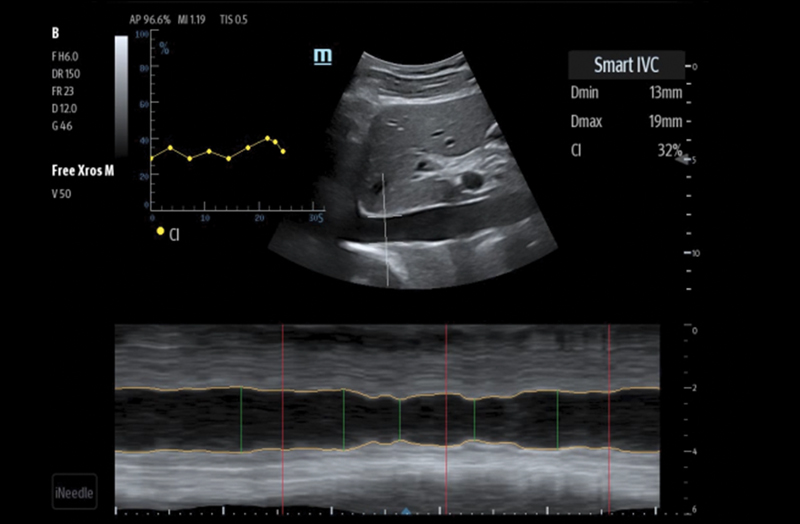

The TE7 Max Ultrasound System is designed to maximize your capabilities in demanding Point of Care environments. With its thoughtful industrial design and best-in-class image quality, the

TE7 Max provides a superior user experience during rapid clinical assessments and procedures taking place at the patient’s bedside

or on the go.

The TE7 Max boasts a large 21.5” vertically oriented high-definition display and a sealed touch-based interface to optimize visualization and accessibility when every second counts. The TE7 Max also incorporates a comprehensive suite of artificial intelligence (AI) powered Smart Tools and workflow enhancement software (iWorks™ Protocol) making efficiency and reproducibility the expectation for all end users.